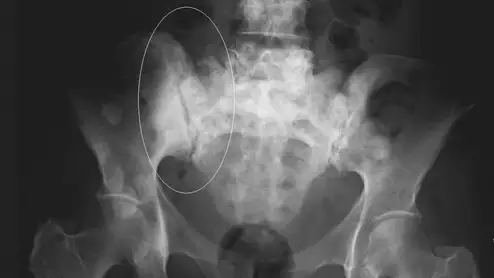

Thanks to AI, clinicians can use mammograms to do a lot more than identify signs of breast cancer. Researchers explored data from nearly 50,000 patients, presenting their findings in Heart.